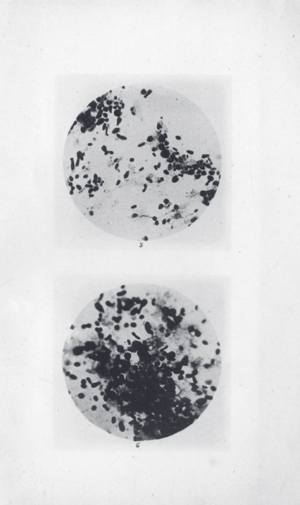

Y. pestis isolated by Ricardo Jorge (pt) during the 1899 Porto plague outbreak

In 1894, two bacteriologists, Alexandre Yersin of Switzerland and Kitasato Shibasaburō of Japan, independently isolated in Hong Kong the bacterium responsible for the Third Pandemic. Though both investigators reported their findings, a series of confusing and contradictory statements by Kitasato eventually led to the acceptance of Yersin as the primary discoverer of the organism. Yersin named it Pasteurella pestis in honor of the Pasteur Institute, where he worked. In 1967, it was moved to a new genus and renamed Yersinia pestis in his honor. Yersin also noted that rats were affected by plague not only during plague epidemics, but also often preceding such epidemics in humans and that plague was regarded by many locals as a disease of rats; villagers in China and India asserted that when large numbers of rats were found dead, plague outbreaks soon followed.[بحاجة لمصدر]